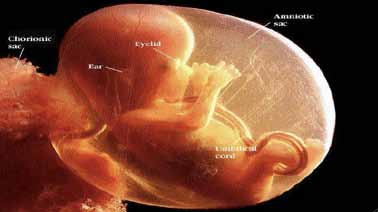

FO : Choroïdite Multifocale avec atteinte de l’épithélium pigmentaire. Angiographie : fluorescence tardive de la choriocapillaire. OCT : Œdème maculaire avec décollement séreux rétinien. (Source iconographie : auteur).